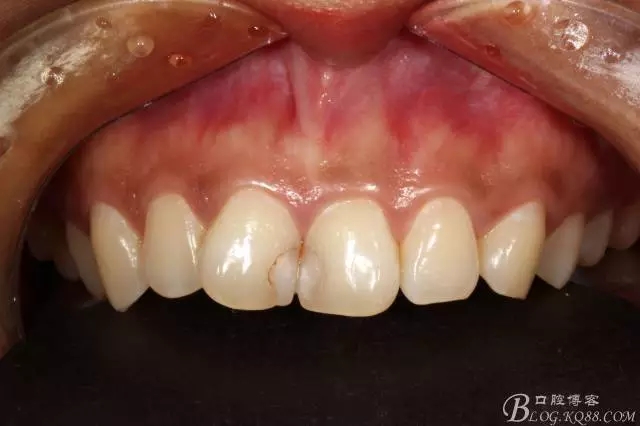

2012年2月接診是的情況

主訴:門牙中間有蛀牙,變色發(fā)要求處理。

檢查就是11、21相鄰面齲壞,